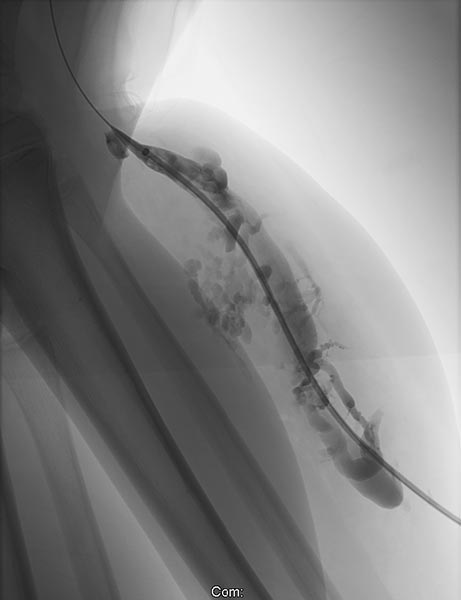

Phlebography after direct puncture of the venous malformation shows a large-lumen drainage vein communicating with the popliteal vein in the popliteal fossa. This must be occluded before sclerotherapy, otherwise the sclerosing agent could unintentionally dislocate through this communication and potentially cause thrombosis of the deep venous system of the leg and/or pulmonary embolism. In addition, there is an ongoing, increased risk of thromboembolism in this patient even outside of sclerotherapy, which can be significantly reduced by occlusion of the communication.

To occlude the vein, a large-lumen introducer sheath is first advanced via a guidewire. This sheath is used to insert the laser fiber and is advanced via the vein to the communication point in the popliteal fossa.

A laser fiber is advanced through this sheath for endovascular laser therapy. The heat of the laser beam causes massive irritation of the vein wall, which subsequently closes quickly. Thrombus formation immediately occurs around the laser tip.

After occlusion via laser fiber and contrast injection via the pulled-back introducer sheath, there is no more outflow of the contrast medium via the communicating vein. Thus the communication is successfully occluded. Only the venous malformation is still contrasted. This is now ready for sclerotherapy, as the sclerosing agent can no longer drain into the deep venous system of the leg.